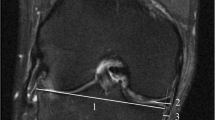

In both the MRI reports and operative notes from arthroscopic surgery, the articular surfaces of the knee were divided into six regions (patella, trochlea, medial femoral condyle, medial tibial plateau, lateral femoral condyle, and lateral tibial plateau). The MRI reports were structured, and the arthroscopy reports were freeform. All data for this study were only obtained from MRI and arthroscopy reports; neither images from the MR nor stored images from arthroscopies were evaluated routinely. MRI and arthroscopic descriptions of each articular surface were both classified using a modified Outerbridge classification, which is the system used by the orthopedic surgeons at this institution (Fig. 1). The adaptation of the Outerbridge classification is defined as follows: grade 0 is normal; grade I is heterogeneous signal (correlating to cartilage softening at arthroscopy); grade II is superficial fissuring, thinning, or defect <50% in depth; grade III is deep fissuring, thinning, or defect >50% in depth; grade IV is a full thickness defect. All musculoskeletal radiologists in the department are familiar with this staging system, and all routinely use descriptive terminology to describe the articular cartilage that would allow easy conversion to the Outerbridge classification. If two or more lesions were present on a single articular surface, the highest-graded lesion was recorded. If a specific articular surface was not explicitly described in the arthroscopy report or if several articular surfaces were described with a blanket statement such as “the remainder of the articular surfaces appeared normal,” then these unnamed articular surfaces were presumed normal. All data were entered into an Excel (Microsoft Corp., Seattle, WA) spreadsheet.

MRI performed at 3.0 T with an apparent far-posterior cartilage abnormality of the lateral femoral condyle. Arthroscopy performed 29 days later did not reveal any cartilage defects. Sagittal PD SPACE (left image) and axial T2-weighted image with fat suppression (right image) demonstrate signal heterogeneity and superficial fissuring of the far posterior non-weightbearing lateral femoral condyle with subchondral cystic change. This region of the far posterior femoral condyle may not be visible during routine arthroscopy. In the current study, this was classified as a false-positive MR grade II lesion